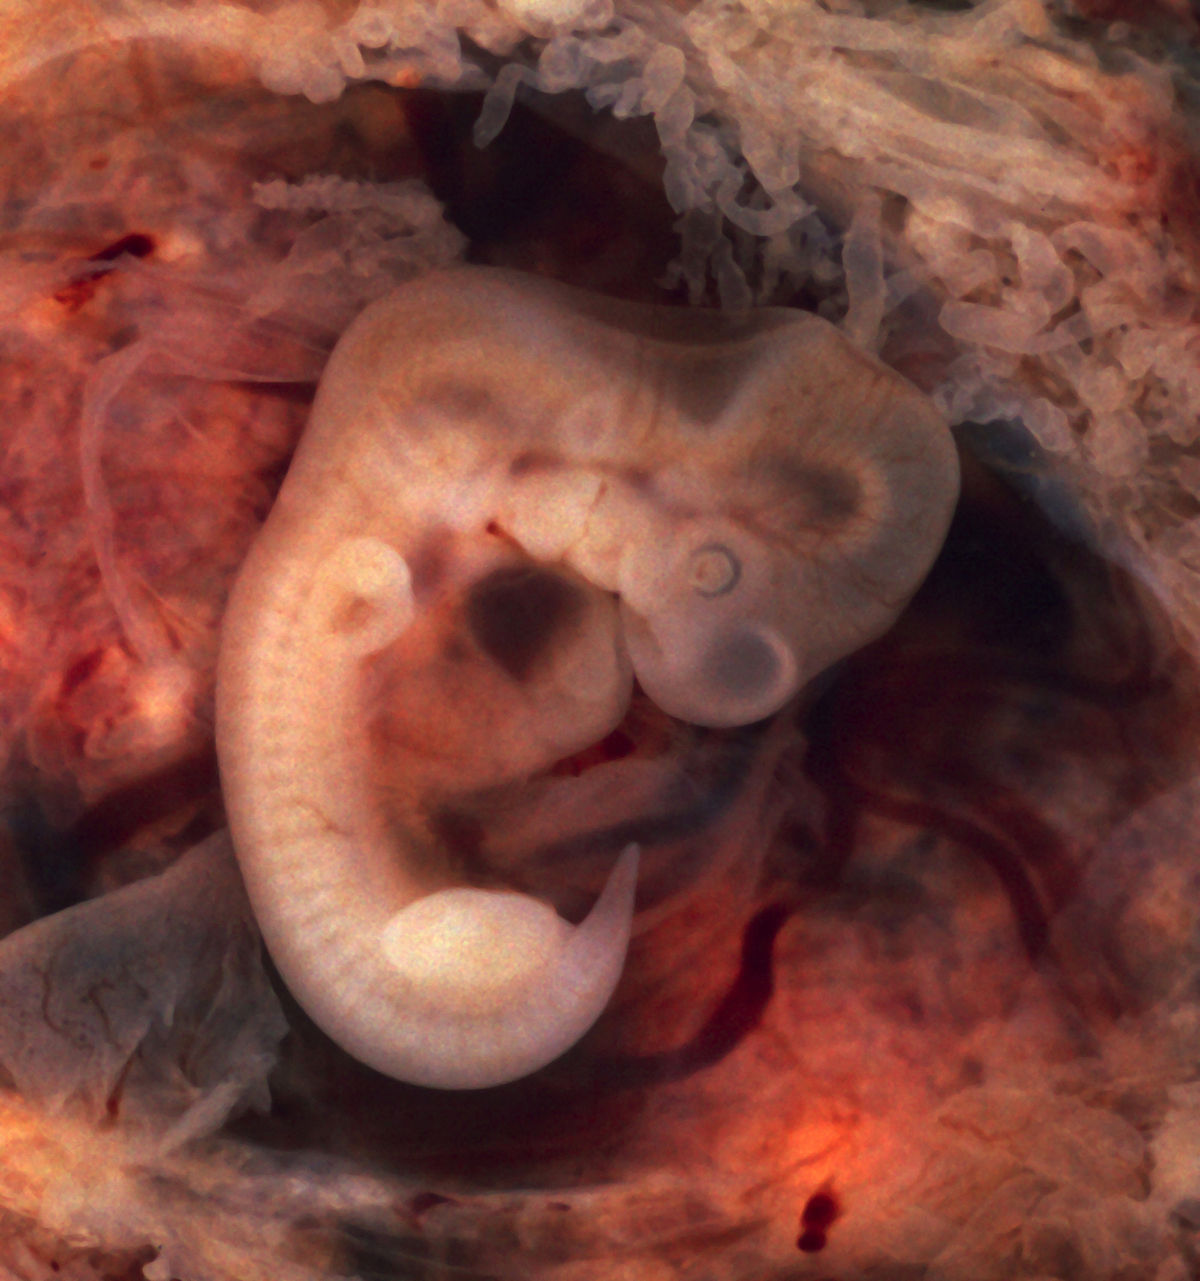

Зарождение жизни: Фотографии Леннарта Нильсона